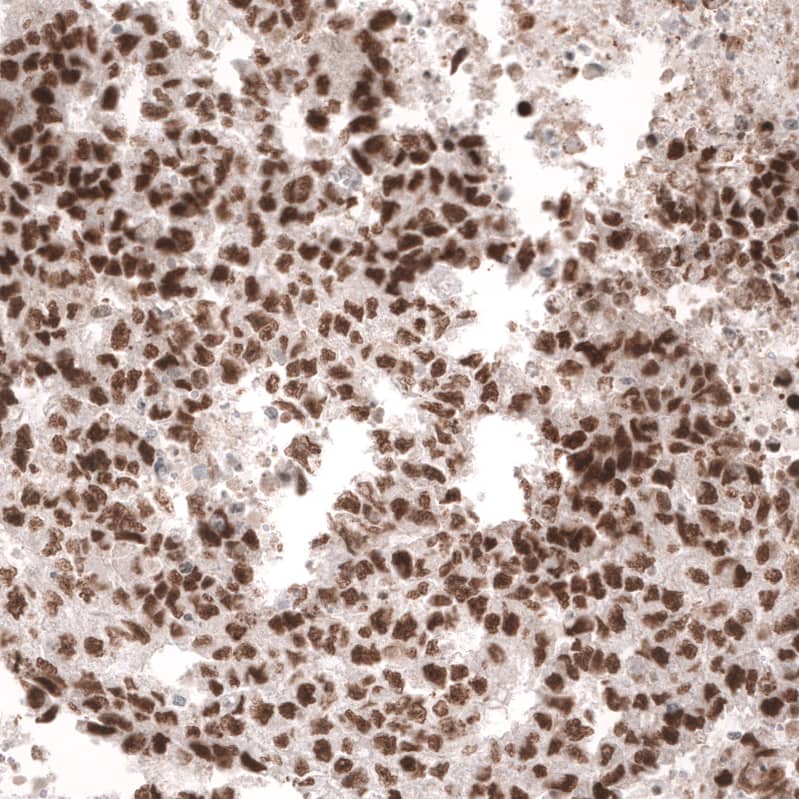

Immunohistochemistry-Paraffin: MSH6 Antibody (CL13844) [NBP3-24582]

Staining of human skeletal muscle shows no positivity in myocytes as expected.